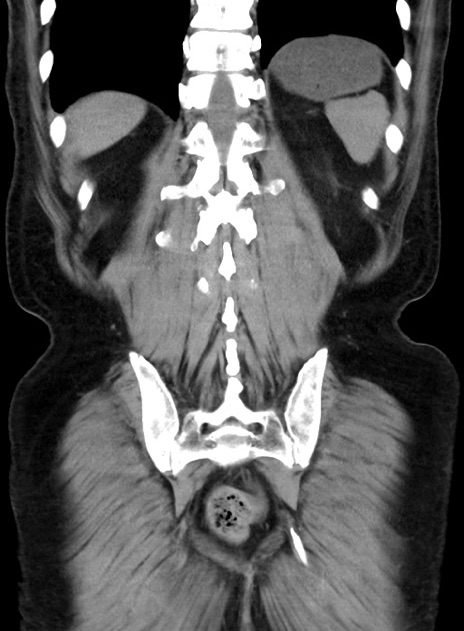

症例38(冠状断像)

【症例】70歳代 男性

【主訴】腹痛・嘔吐

【現病歴】昨晩より、嘔吐・腹痛あり。今朝になっても嘔吐あり。来院。

【既往歴】心臓バイパス手術、開腹胆摘、腸閉塞

【身体所見】BP 107/71mmHg、HR 116/min、腹部:平坦、軟、下腹部に軽度圧痛あり。反跳痛なし。

【データ】WBC 15100、CRP 0.32